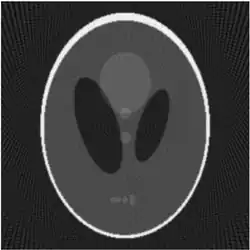

If a function represents an unknown density, then the Radon transform represents the projection data obtained as the output of a tomographic scan. Hence the inverse of the Radon transform can be used to reconstruct the original density from the projection data, and thus it forms the mathematical underpinning for tomographic reconstruction, also known as iterative reconstruction.

The process of reconstruction produces the image (or function in the previous section) from its projection data. Reconstruction is an inverse problem.

In the two-dimensional case, the most commonly used analytical formula to recover from its Radon transform is the Filtered Back-projection Formula or Radon Inversion Formula[9]: where is such that .[9] The convolution kernel is referred to as Ramp filter in some literature.

Compared with the Filtered Back-projection method, iterative reconstruction costs large computation time, limiting its practical use. However, due to the ill-posedness of Radon Inversion, the Filtered Back-projection method may be infeasible in the presence of discontinuity or noise. Iterative reconstruction methods (e.g. iterative Sparse Asymptotic Minimum Variance[10]) could provide metal artefact reduction, noise and dose reduction for the reconstructed result that attract much research interest around the world.

Explicit and computationally efficient inversion formulas for the Radon transform and its dual are available. The Radon transform in dimensions can be inverted by the formula:[11] where , and the power of the Laplacian is defined as a pseudo-differential operator if necessary by the Fourier transform: For computational purposes, the power of the Laplacian is commuted with the dual transform to give:[12] where is the Hilbert transform with respect to the s variable. In two dimensions, the operator appears in image processing as a ramp filter.[13] One can prove directly from the Fourier slice theorem and change of variables for integration that for a compactly supported continuous function of two variables: Thus in an image processing context the original image can be recovered from the 'sinogram' data by applying a ramp filter (in the variable) and then back-projecting. As the filtering step can be performed efficiently (for example using digital signal processing techniques) and the back projection step is simply an accumulation of values in the pixels of the image, this results in a highly efficient, and hence widely used, algorithm.